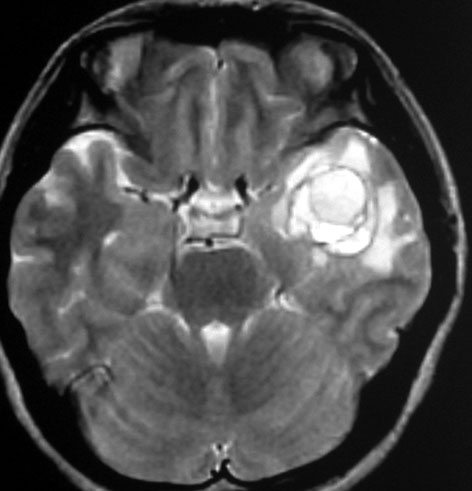

左上のT2*でみられるように多発性海綿状血管腫の成人男性に発生した中脳海綿状血管腫です。複視と歩行失調で発症して,数回の脳幹部出血を繰り返し,水頭症になったために第3脳室開窓術がなされました。それでも出血は止まらず、両側の動眼神経麻痺による両側眼瞼下垂,歩行失調,嚥下障害などさまざまな中脳症状が進行しました。

しかたがないので手術で摘出しました。なんとか眼瞼が持ち上がるようになり歩行も可能で嚥下もできます。幸いだったのは感覚路(脊髄視床路)の障害による体性疼痛が生じなかったことです。

手術は経テント法 OTA という手法でした(クリックと手技が書いてあります)

片方の下丘の損傷だけでは神経脱落症状が出ないので,中脳内部の腫瘍を摘出するには下丘という狭い場所を切開して入りますが,この患者さんは左上丘も出血のために破壊されていて,間口が広かったといえます。でもこの手術は難しすぎるので決して積極的にはしません。